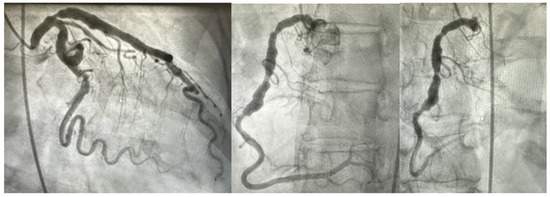

2. Clinical Features